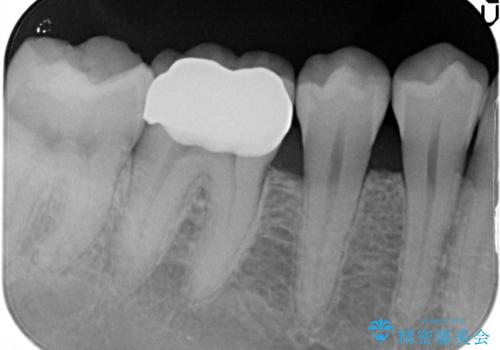

やはり内部では少量の虫歯がありましたので、拡大鏡使用して虫歯を除去しました。

今回精度の高い治療を行うことで、再治療の可能性を限りになく小さくできました。